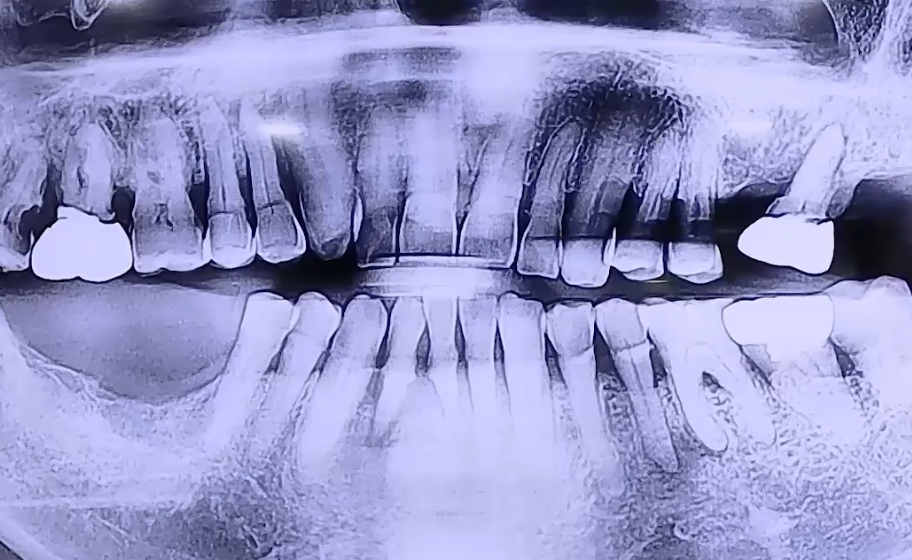

BEFORE

아래 앞니의 통증을 호소하며 내원해 주셨던 환자분이십니다.

통증을 느끼는 쪽 치아가 흔들리고 계셨고, 오른쪽 아래 어금니가

예전에 발치하셔서 없으며 왼쪽은 위 어금니가 하나만 남아있었는데요.

오른쪽 아래 어금니가 없기 때문에 오랫동안 왼쪽으로 식사하신 영향으로

왼쪽 치아 상태도 점점 약해지면서 앞니 쪽으로 식사를 하게 되셨던 것으로 확인되었습니다.